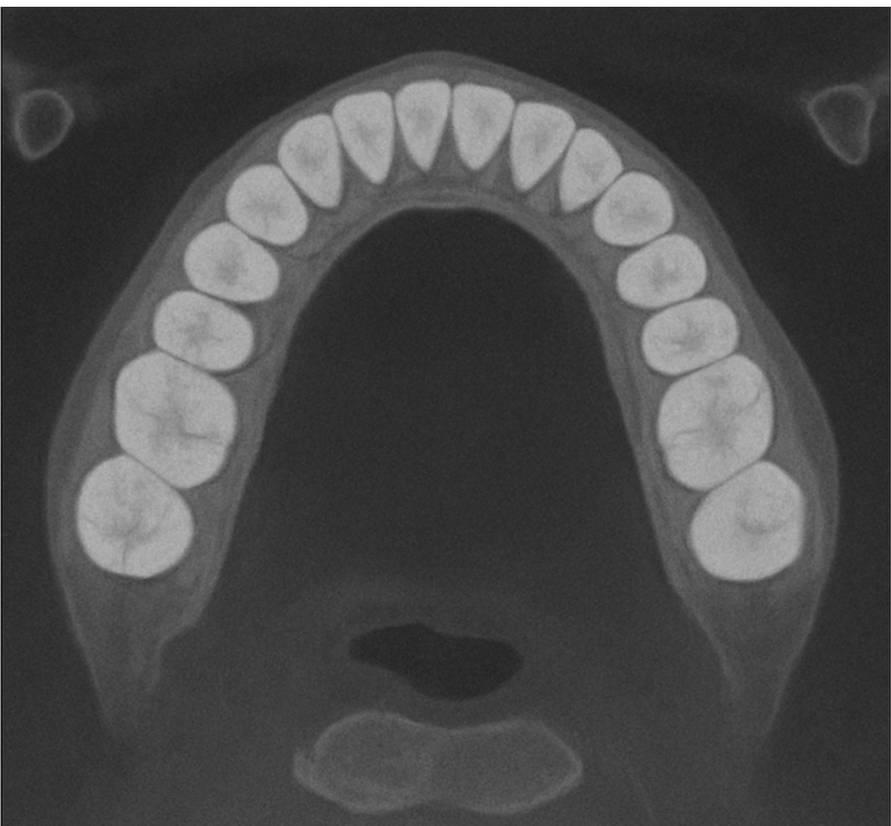

The Panoramic OP 3D LX is an advanced dental imaging system designed to provide a complete, high-resolution view of your entire mouth in a single image. This technology captures your teeth, jawbones, and surrounding structures with remarkable clarity, helping dentists identify issues such as cavities, infections, bone loss, and impacted teeth. Its quick, comfortable process makes it an excellent tool for routine check-ups, pre-treatment evaluations, and surgical planning. The OP 3D LX minimizes patient radiation exposure while maximizing diagnostic accuracy, ensuring a safe and effective experience for every patient.